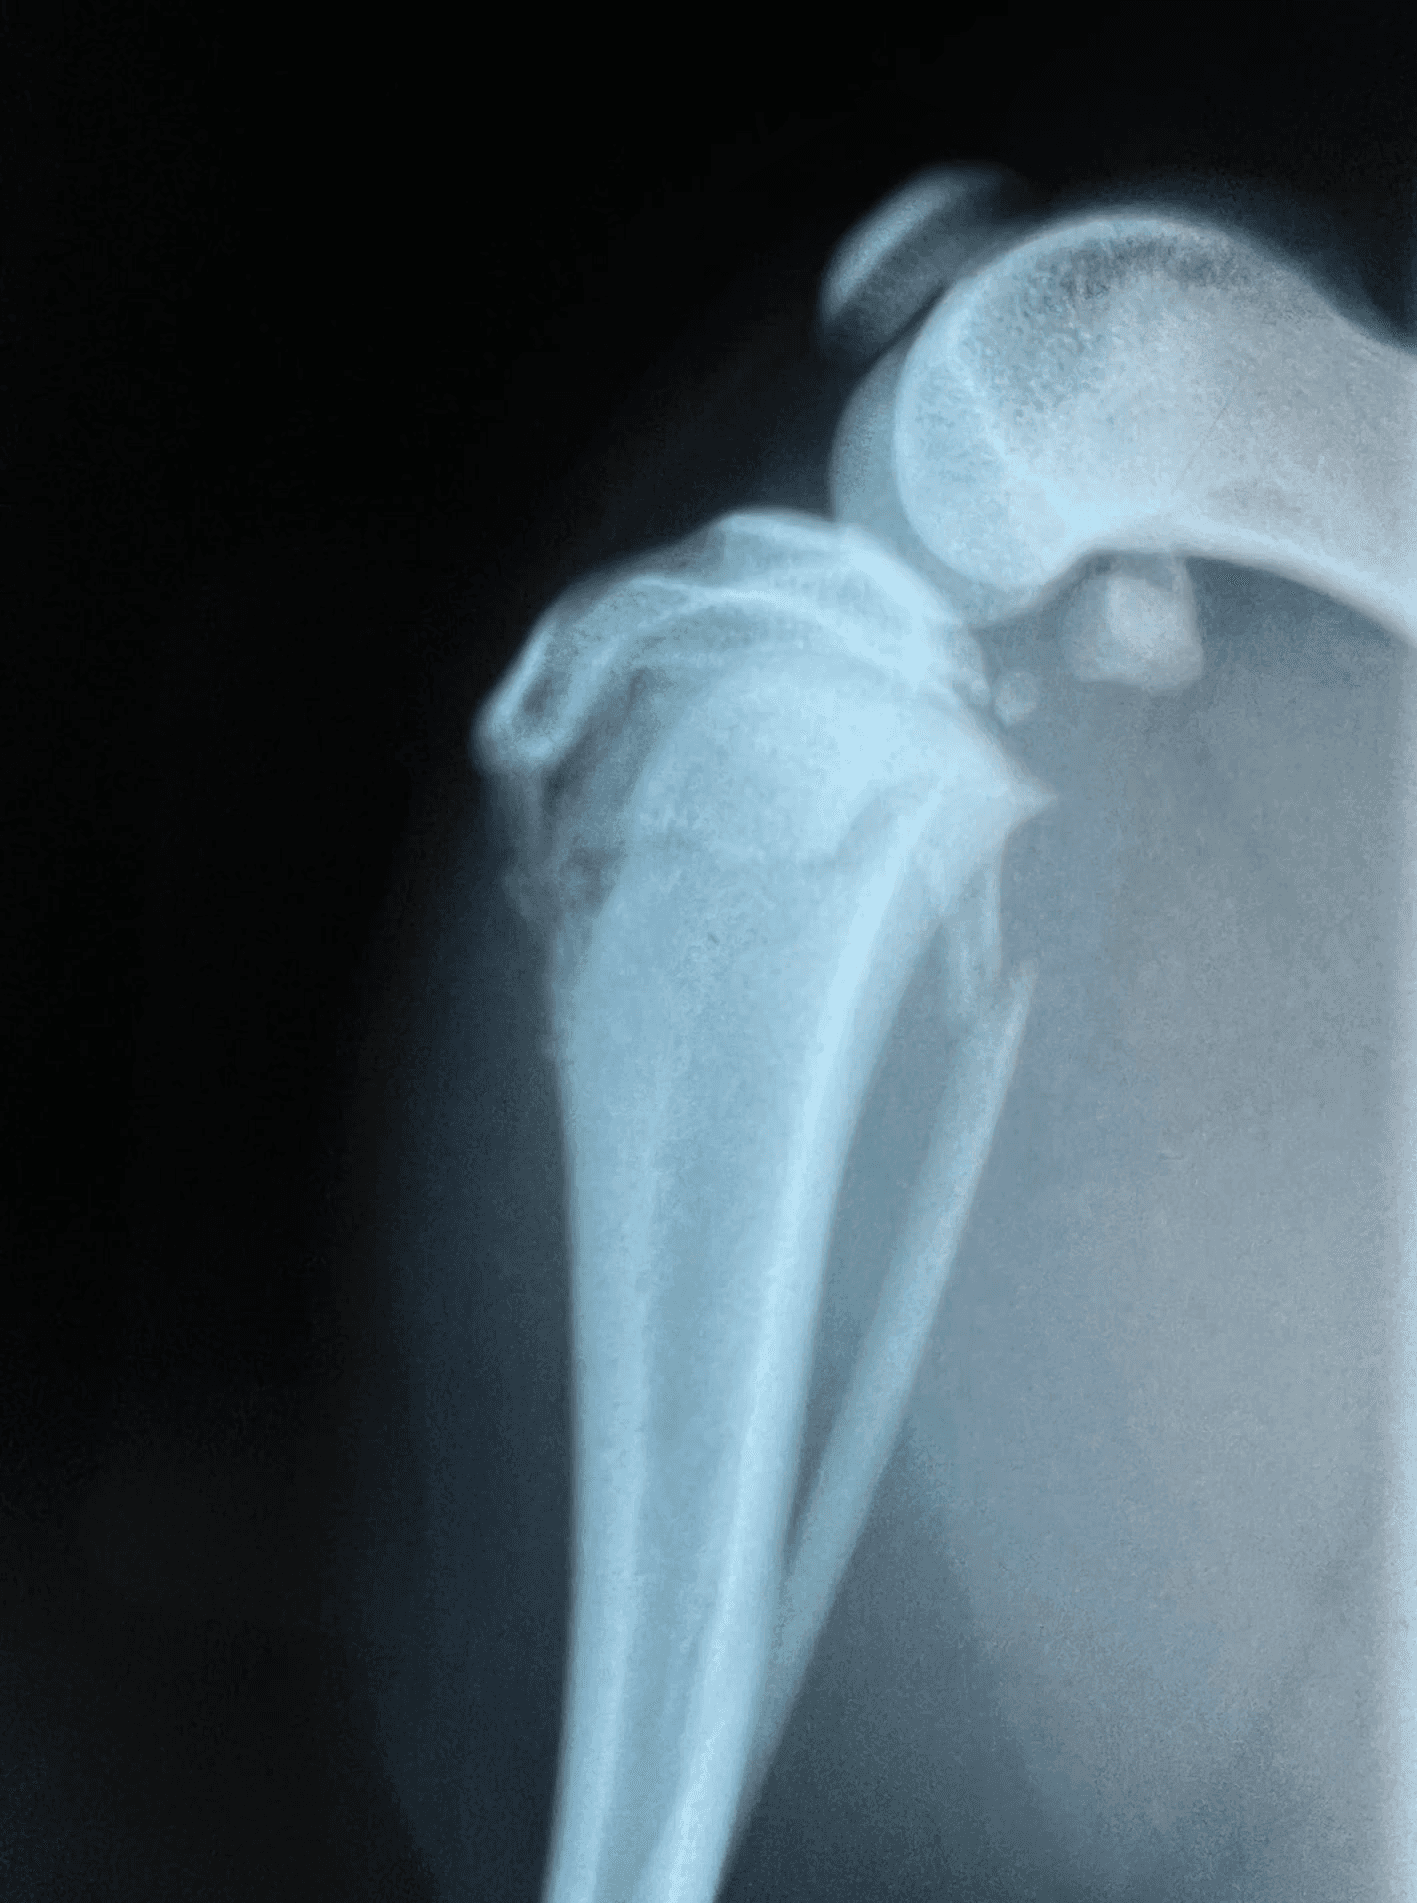

X-rays of the injured area are required to confirm the fracture and determine the best treatment approach. At least two straight views (lateral and cranial/caudal) are necessary for all fractures because a single view can disguise or miss the problem. Pain relief and sedation medications are often needed to obtain accurate X-ray images comfortably and safely.

Elbow Luxation with chip fracture missed on single view